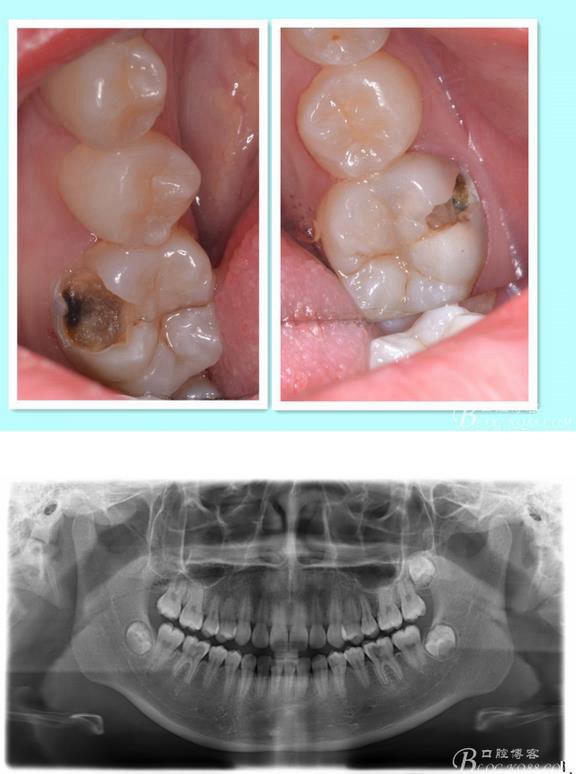

主訴:雙側(cè)下后牙疼痛一月余

病史:近一個月雙側(cè)下后牙疼痛,自發(fā)性 陣發(fā)性鈍痛,進食嵌塞加重,求診

查:雙側(cè)下6頰HE面齲壞 探診疼痛 冷熱刺激 遲反應疼痛 叩診(-)頰側(cè)齲壞平齦

X線:雙側(cè)下6 齲壞已接近髓腔

診斷:雙側(cè)下6 慢性牙髓炎

治療方案:雙側(cè)RCT+CAD-CAM

這里我單做右側(cè)的詳細步驟